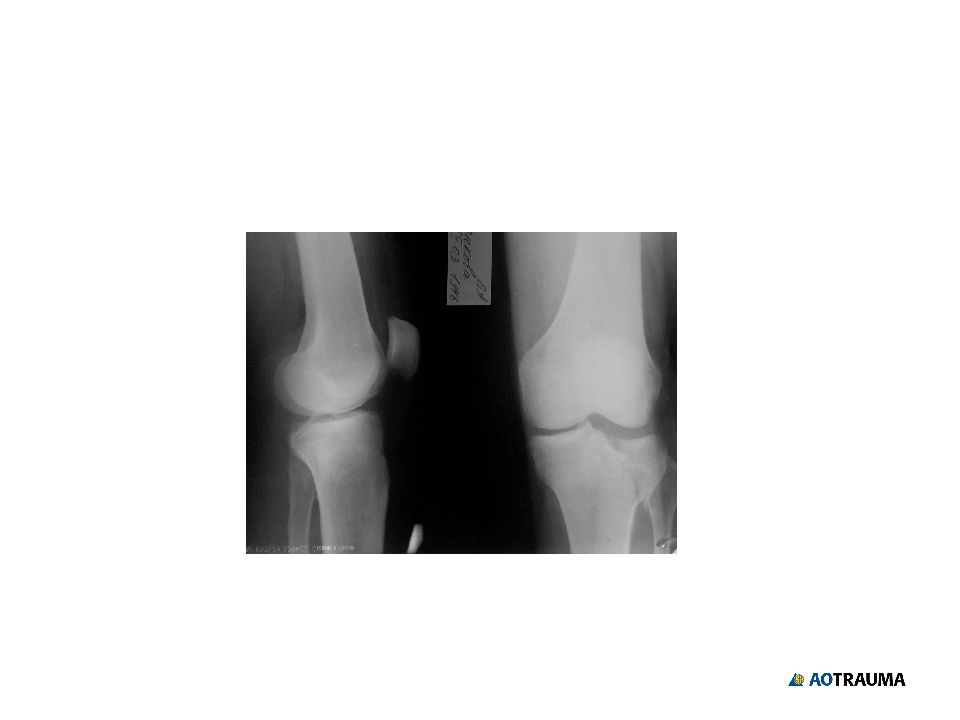

Слайд 26

Кость - 4 Сегмент Тип группа